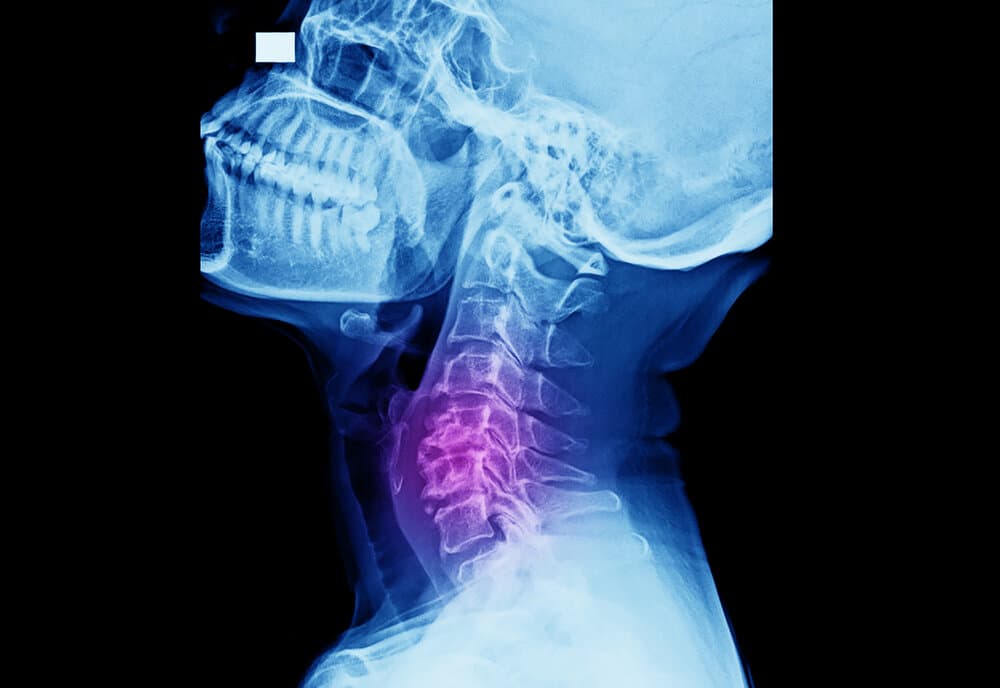

انحلال الفقرات

اعتلال الجذور العصبية: الأسباب والأعراض والتشخيص والعلاج